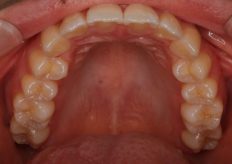

Before

After

| 症状 | 上顎前歯部叢生 |

| 治療内容 | インビザライン アライナー |

| 治療期間 | 10か月 |

| 費用 | 509,000円 |

上の前歯が曲がっている前に出ているのが気になるとのことで来院されました。

今回の矯正治療は上の前歯のみと審美性に考慮して歯の表に装置を付けるのではなくマウスピースで行ってほしいとのことでの依頼です。

前歯の叢生もさほどひどくないのでIPR(歯と歯の間を少し削る)を行いとても良い感じの仕上がりでとても満足していただけました。

マウスピースの矯正は食事する時と歯磨きする時以外は装着していただければかなりいい感じに歯並びが仕上がると思います

大阪府 茨木市 28歳 女性